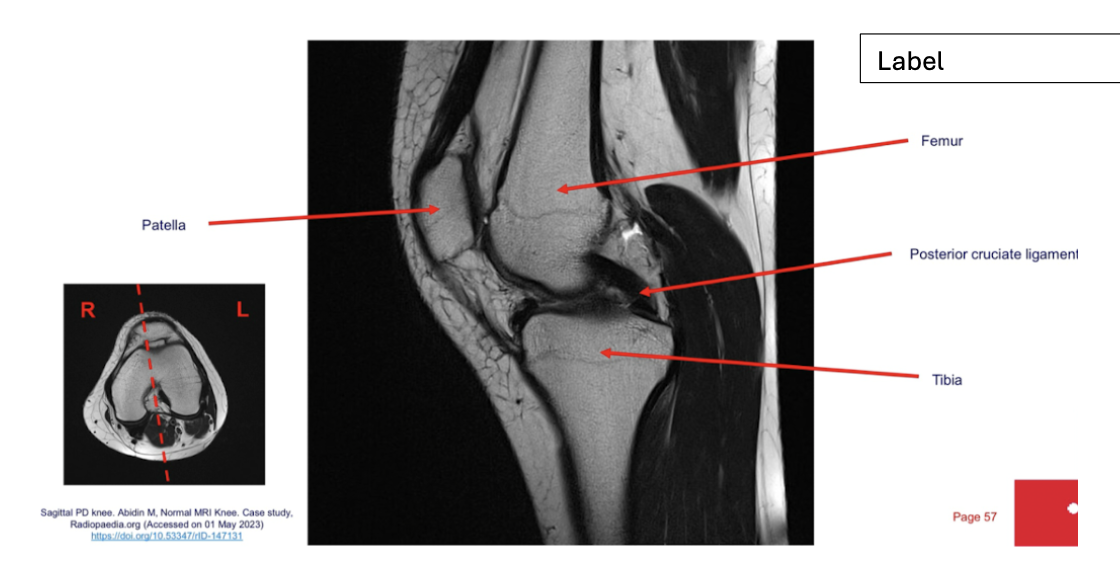

label each

2- lateral and medial condyles of femur

4- vastus lateralis muscle

5-posterior cruciate ligament

6- anterior cruciate ligament

7- medial meniscus of knee

8- lateral meniscus of knee

9-tibia

10-fibula

label

Sequence + Why?

PD- proton density

• Fat is bright, fluid is bright, intermediate signal from muscle.